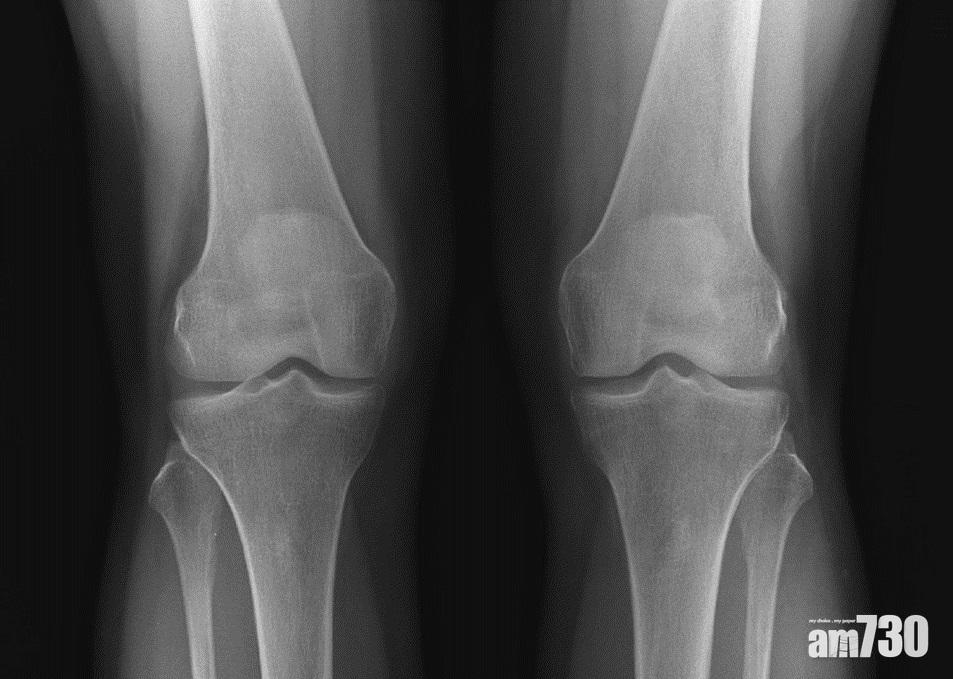

當膝關節的軟骨嚴重磨蝕,甚至出現骨磨骨情況,屆時患者就要接受關節置換手術。李醫生指出,過去較常用的「全膝關節置換手術」,成效顯著,但它的缺點是,即使患者不是整個關節出現退化,也得把全個關節換走,一併把正常組織完全移除,對患者而言並非最大效益,故衍生出「半膝關節置換手術」,只換走需要移除的部份,保留健全的組織。

退化性關節(左)的軟骨層遭磨蝕,距離較正常的關節(右)少,嚴重可出現骨磨骨的情況。(圖片由醫生提供)